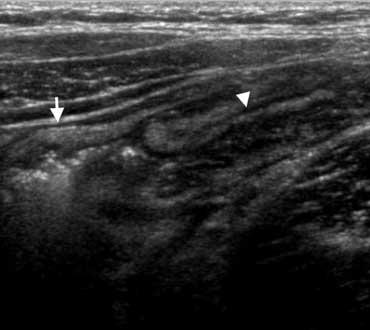

Siêu âm điển hình cho thấy dày thành dưới niêm mạc (đầu mũi tên) của hồi tràng đoạn cuối và manh tràng mà không có viêm mỡ xung quanh.

Viêm hồi manh tràng do vi khuẩn

Viêm ruột nhiễm khuẩn có thể gây ra các triệu chứng nhẹ giống viêm dạ dày ruột do virus thông thường, nhưng cũng có thể biểu hiện lâm sàng với các đặc điểm không thể phân biệt được với viêm ruột thừa, đặc biệt trong viêm hồi manh tràng do vi khuẩn, gây ra bởi Yersinia, Campylobacter hoặc Salmonella.

Dấu hiệu chính: Dày thành hồi manh tràng không kèm viêm mỡ, hạch to, ruột thừa bình thường